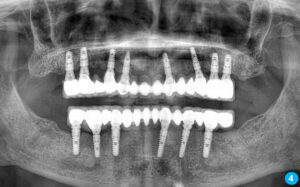

İlk aşamada implant çene kemiğine yerleştirilir. Ardından ortalama 3 ay kadar kişiden kişiye değişiklik gösteren bekleme süreci olur. Bekleme sürecinin amacı kemik oluşumu ve implantın çene kemiğine kaynaşmasını sağlamaktır. Bu süreç bittikten sonra implantın üst yapısının yapılması ise 1-2 haftalık bir zamanda bitmektedir.

Diş çürüğü, diş eti hastalığı, dental travma, diş çekimi, dişlerin sallanması gibi sebeplerle kaybedilen dişlerin yerine kuron-köprü uygulamalarıyla bu eksiklikler tamamlanabilmektedir. köprü uygulaması için kişinin en az sağlam iki dişinin kesilip boyutsal olarak küçültülmesi gerekmektedir ve bu uygulamanın geri dönüşü yoktur. İmplant ise sağlam dişlere dokunulmadan sadece diş boşluğu kullanılarak uygulanan bir tedavidir.

Alt-üst damakta hiç dişi olmayan hastalar hareketli proteze alışamamakta, bulantı reflefsi oluşturmakta ve çoğu hastada damaklar ağızda sıkı bir şekilde durmamaktadır. Bu durum hastaları sosyal yönden olumsuz etkilyebilmektedir. Hiç dişi olmayan hastalara implant önemli bir çözüm oluşturmaktadır.